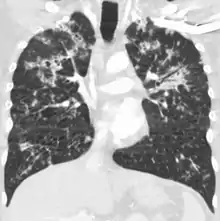

Miliary tuberculosis is a form of tuberculosis that is characterized by a wide dissemination into the human body and by the tiny size of the lesions (1–5 mm). Its name comes from a distinctive pattern seen on a chest radiograph of many tiny spots distributed throughout the lung fields with the appearance similar to millet seeds—thus the term "miliary" tuberculosis. Miliary TB may infect any number of organs, including the lungs, liver, and spleen.[2] Miliary tuberculosis is present in about 2% of all reported cases of tuberculosis and accounts for up to 20% of all extra-pulmonary tuberculosis cases.[3]

Tuberculosis of the lungs

Testing for miliary tuberculosis is conducted in a similar manner as for other forms of tuberculosis, although a number of tests must be conducted on a patient to confirm diagnosis.[4] Tests include chest x-ray, sputum culture, bronchoscopy, open lung biopsy, head CT/MRI, blood cultures, fundoscopy, and electrocardiography.[10] The tuberculosis (TB) blood test, also called an Interferon Gamma Release Assay or IGRA, is a way to diagnose latent TB. A variety of neurological complications have been noted in miliary tuberculosis patients—tuberculous meningitis and cerebral tuberculomas being the most frequent. However, a majority of patients improve following antituberculous treatment. Rarely lymphangitic spread of lung cancer could mimic miliary pattern of tuberculosis on regular chest X-ray. [15]

A case of miliary tuberculosis in an 82-year-old woman: